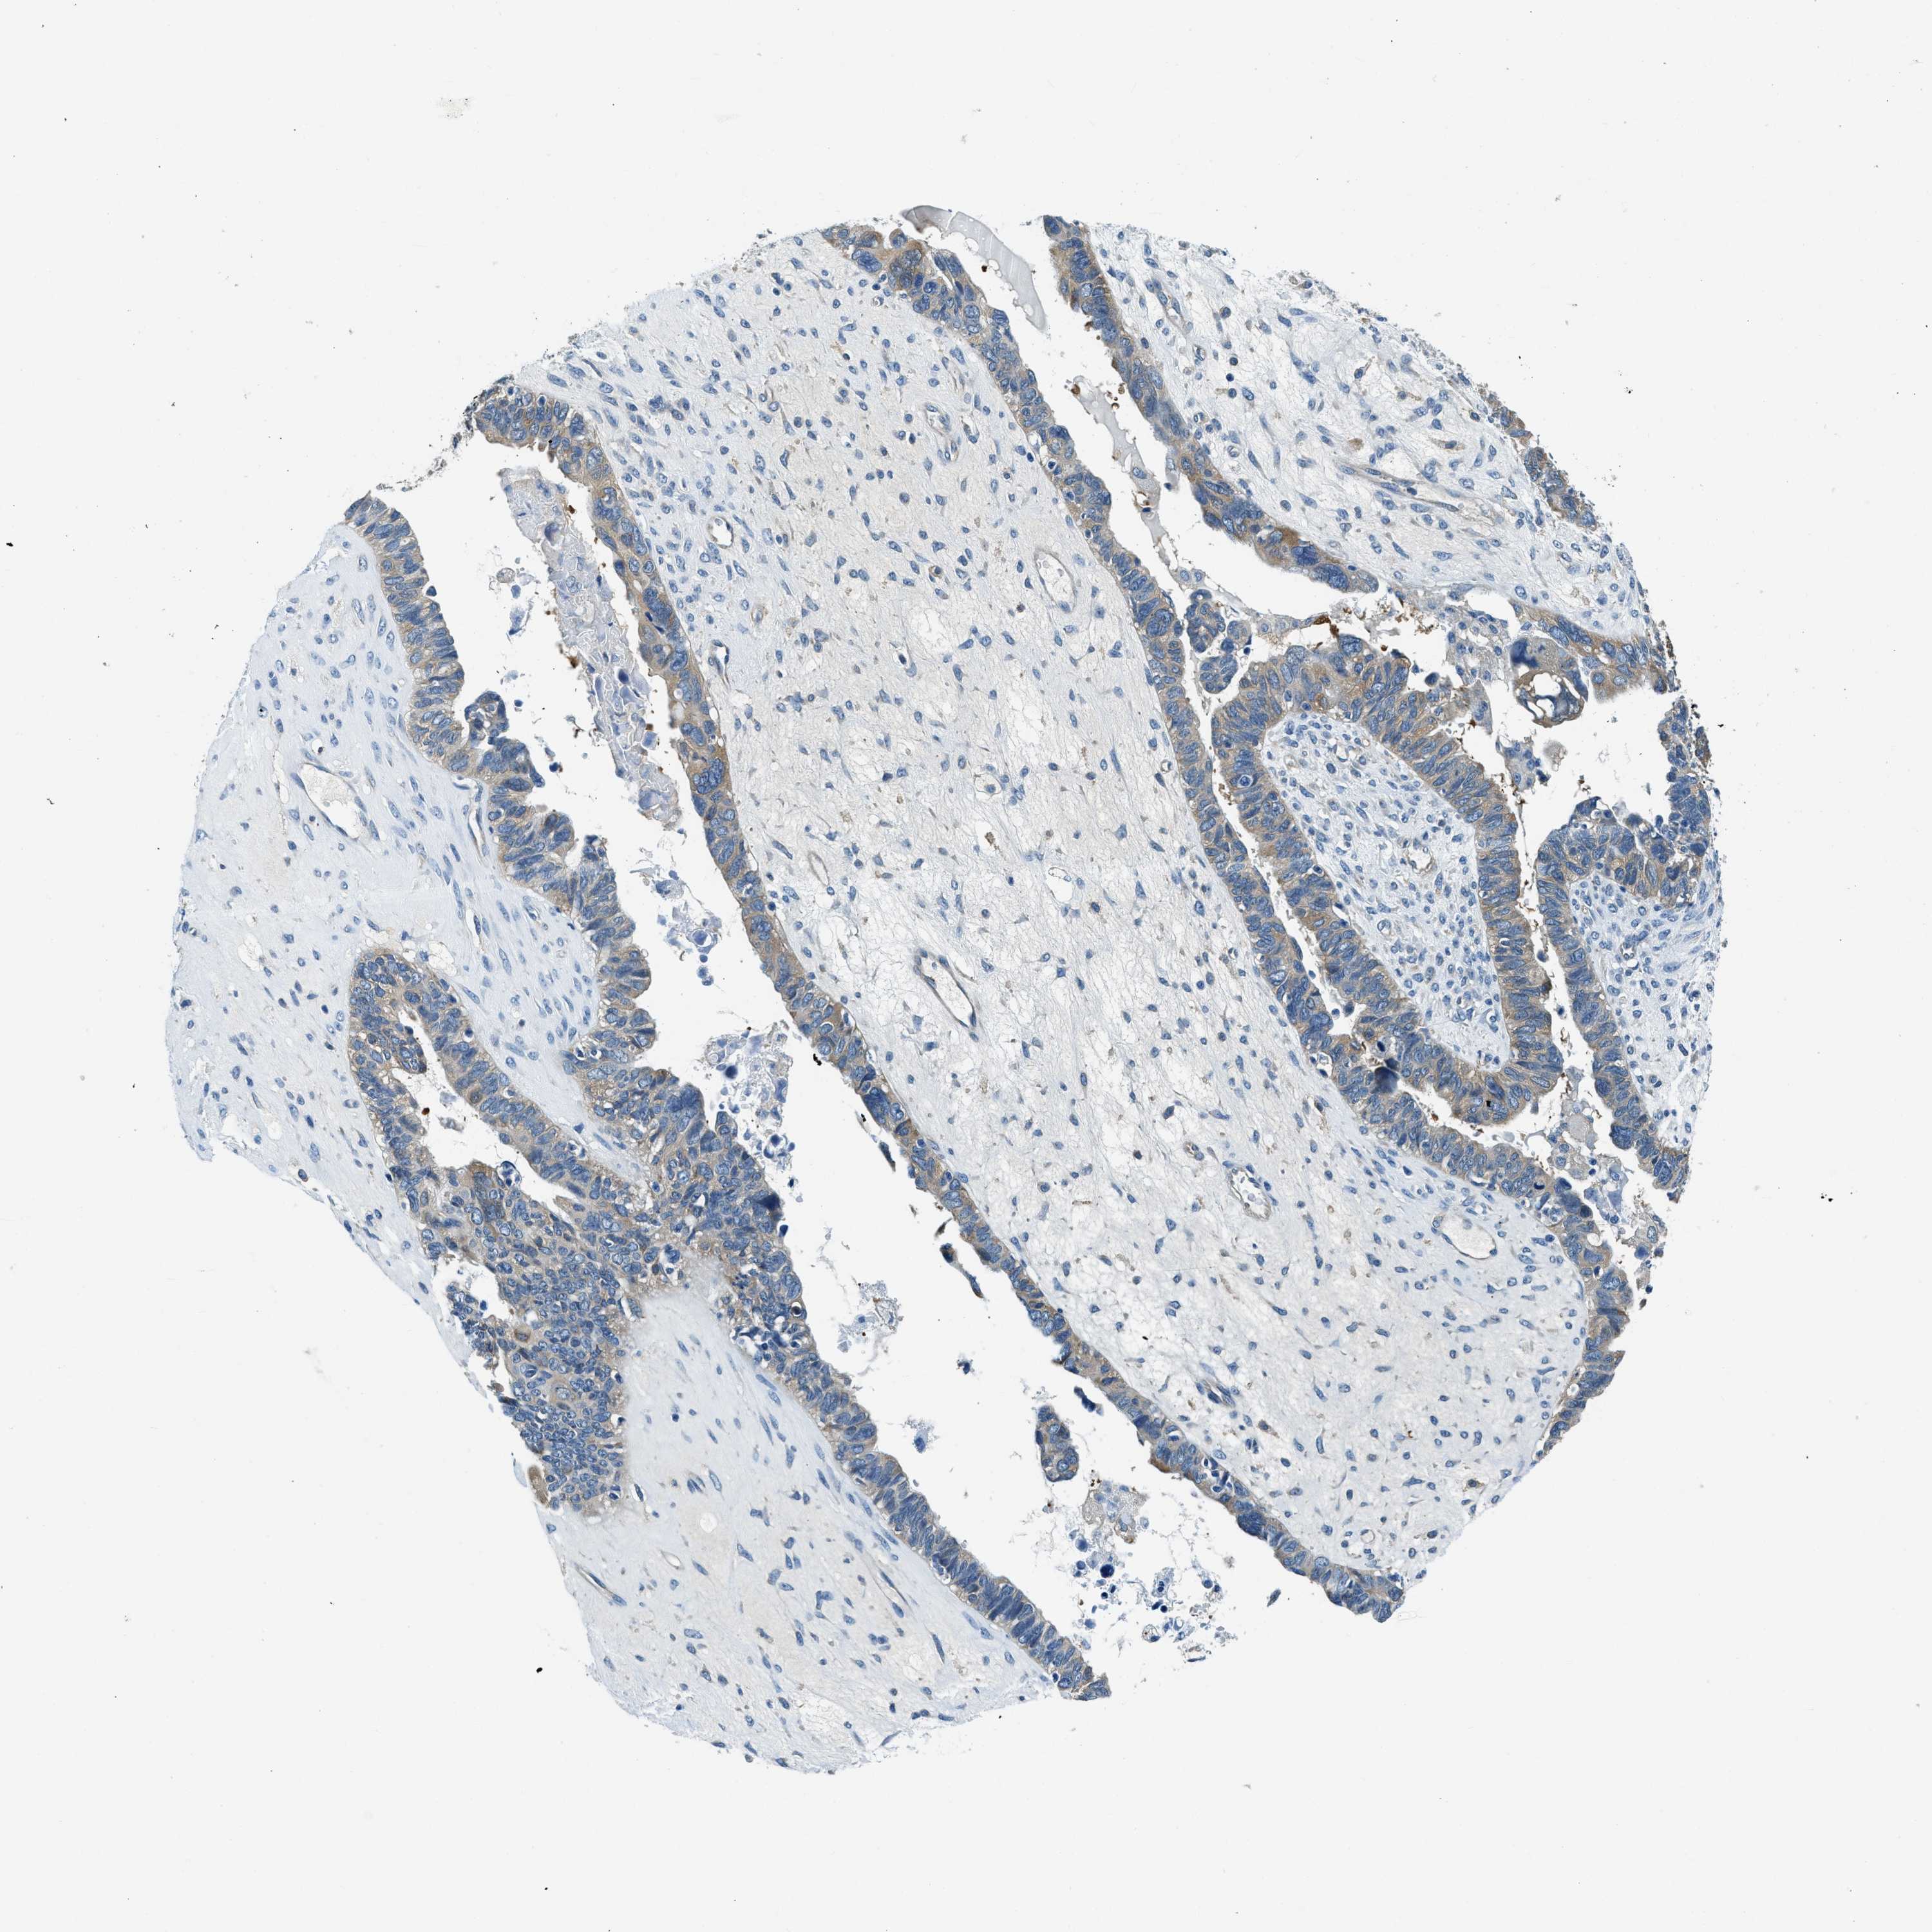

OVARIAN CANCER - Protein expressioni

A mouse-over function shows sample information and annotation data. Click on an image to view it in a full screen mode. Samples can be filtered based on level of antibody staining by selecting one or several of the following categories: high, medium, low and not detected. The assay and annotation is described here.

Note that samples used for immunohistochemistry by the Human Protein Atlas do not correspond to samples in the TCGA dataset.

Antibody stainingi

Antibody staining in the annotated cell types in the current human tissue is reported as not detected, low, medium, or high, based on conventional immunohistochemistry profiling in selected tissues. This score is based on the combination of the staining intensity and fraction of stained cells.

Each image is clickable and will lead to virtual microscopy that enables deeper exploration of all samples and also displays staining intensity scores, fraction scores and subcellular localization as well as patient and tissue information for each sample.

Antibody HPA018116

Staining

High

Medium

Low

Not detected

Intensity

Strong

Moderate

Weak

Negative

Quantity

>75%

75%-25%

<25%

None

Location

Nuclear

Cytoplasmic/membranous

Cytoplasmic/membranous,nuclear

Cystadenocarcinoma, serous, NOS

Carcinoma, endometroid

Cystadenocarcinoma, mucinous, NOS

Carcinoma, NOS